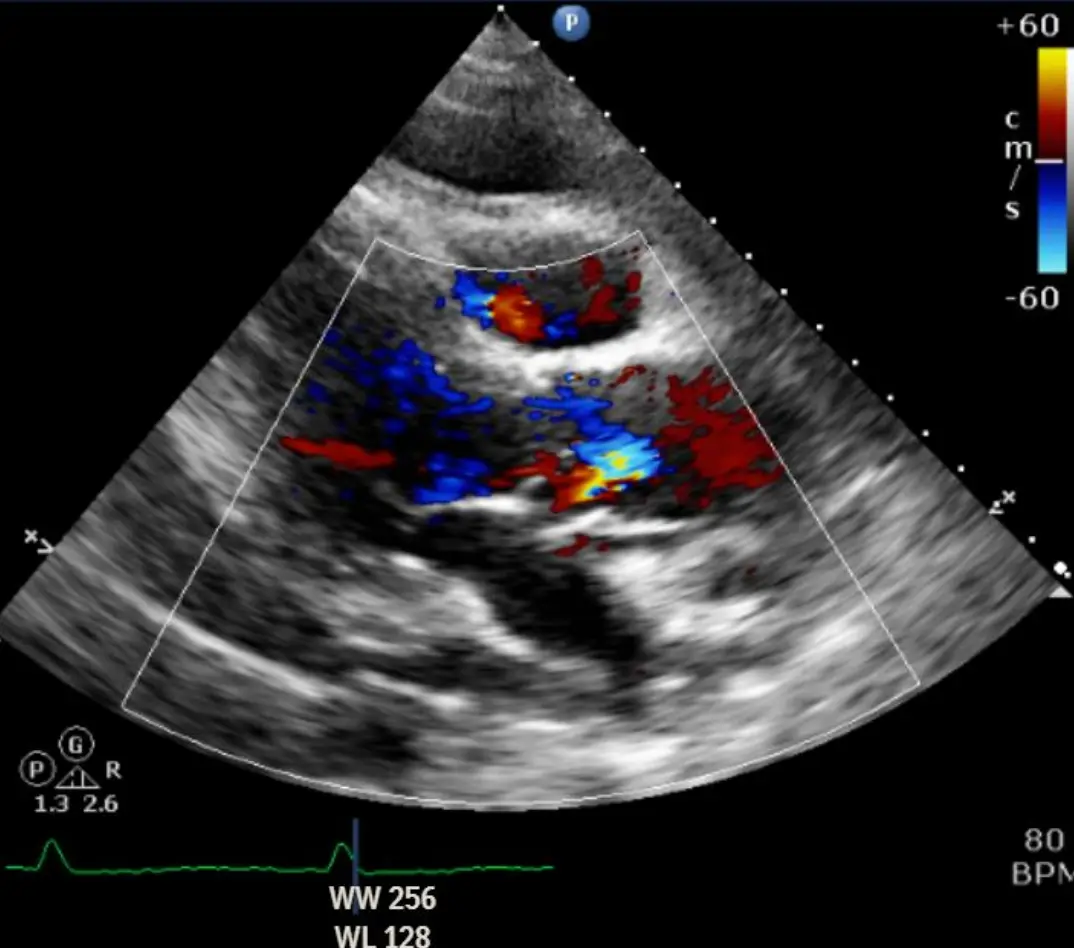

3. Echocardiogram:

• 四腔像可見心肌與心包之間廣泛無回聲帶;右房、右室於早期舒張期呈輕度塌陷。